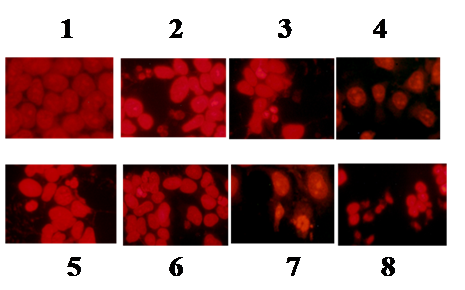

Fluorescence imaging

Effect of kaempferol-doxorubicin/cisplatin combination on apoptotic cell death of cancer cells

On the basis of strong growth inhibition by the synergistic effect of kaempferol-doxorubicin or cisplatin combination on HCT-15 and MDA MB 231 cells, the investigation was carried to show their effect on apoptotic morphological changes. To evaluate the effect of kaempferol and doxorubicin or cisplatin, treated cells were stained with propidium iodide. The results were compared with untreated control cells. The stained cells showed fragmentation and condensation of chromatin and other morphological features characteristic of apoptotic cells in both the cancer cells, whereas untreated control cells were not identified with nuclear alterations and showed a normal nuclear morphology characterised by diffused chromatin structure. The combinational dose concentrations of kaempferol, doxorubicin or cisplatin and treatment design, were the same as that of other studies for both cell lines. As shown in (fig. 7, 8), the apoptotic cell population was increased in both HCT-15 and MDA MB 231 cell lines when treated with doxorubicin or cisplatin in combination with kaempferol.

Apoptotic death of cancer cells is considered to be a potential anti-cancer mechanism, which could control their proliferation [1, 10]. Recently, the regulation of apoptosis has been proposed as a promising target for cancer chemotherapy [19, 20]. Consistent with these reports, the data of our present study show clearly that kaempferol and doxorubicin/cisplatin combination induces strong apoptotic cell death that was ~ 3 fold higher than each agent alone.

Fig. 7: Morphologial alterations of HCT-15 cells treated with kaempferol in combination with chemotherapeutic drugs, cells treated with concentrations. (1) control; (2) kaempferol (120 µg/ml); (3)-doxorubicin (50 µg/ml); (4)-cisplatin (25 µg/ml); (5)-kaemferol (120 µg/ml)+doxorubicin (50 µg/ml); (6)-kaemferol (30 µg/ml) doxorubicin (10 µg/ml); (7)-kaemferol (120 µg/ml)+cisplatin (25 µg/ml); (8)-kaemferol(30 µg/ml)+cisplatin (10 µg/ml). Cells were visualized under fluorescence microscope (Magnification X200)